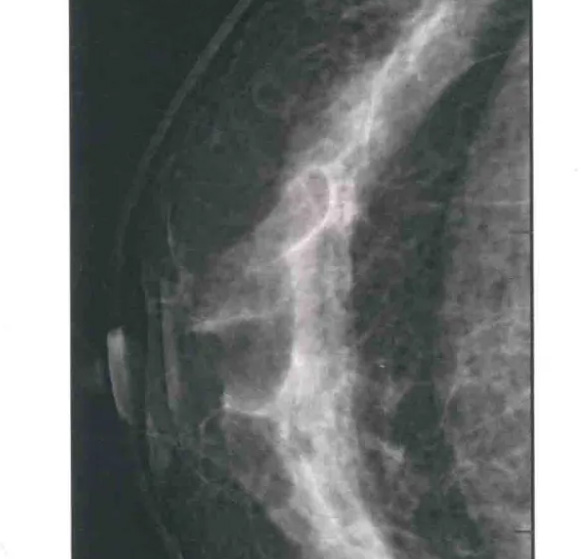

二、图像显示要求,含乳腺的基底部及内外侧乳腺组织,需要显示胸肌前缘或胸壁。头尾位与内外斜位乳头后线长度差≤1厘米;显示实质后的乳腺组织,乳头位于切线位,乳腺组织重叠;双侧乳腺头尾位照片相对放置,则两侧乳腺呈球形;影像密度和对比度良好,能显示0.1毫米细小钙化,清晰没有伪影异物、运动伪影和切割伪影等。